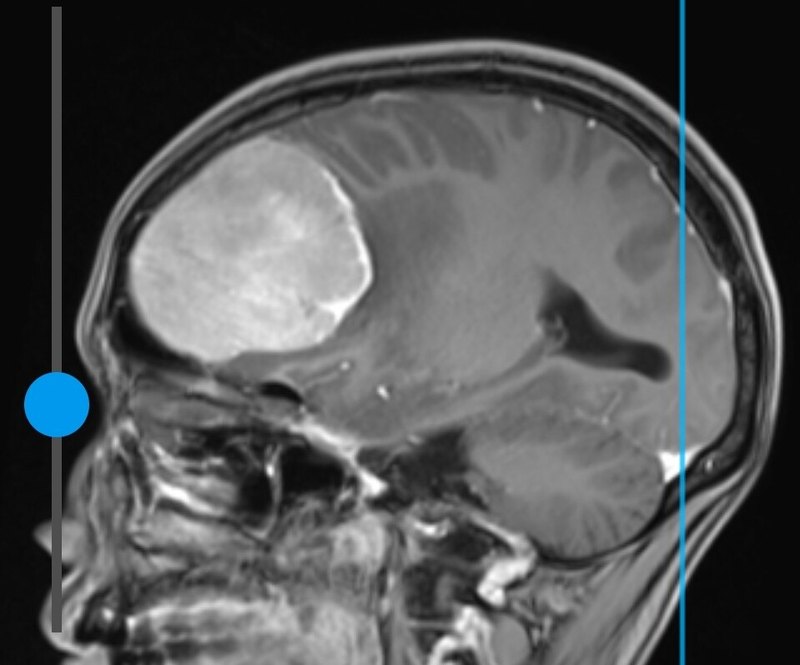

治療前術(shù)前核磁顯示腫瘤約4X5X5cm大小,手術(shù)大部切除后三月復查腫瘤明顯縮小,頭痛惡心嘔吐癥狀消失,恢復正常生活工作。治療中術(shù)后三月復查核磁顯示腫瘤明顯縮小治療后治療后3月患者頭痛、惡心癥狀消失,恢復正常生活工作